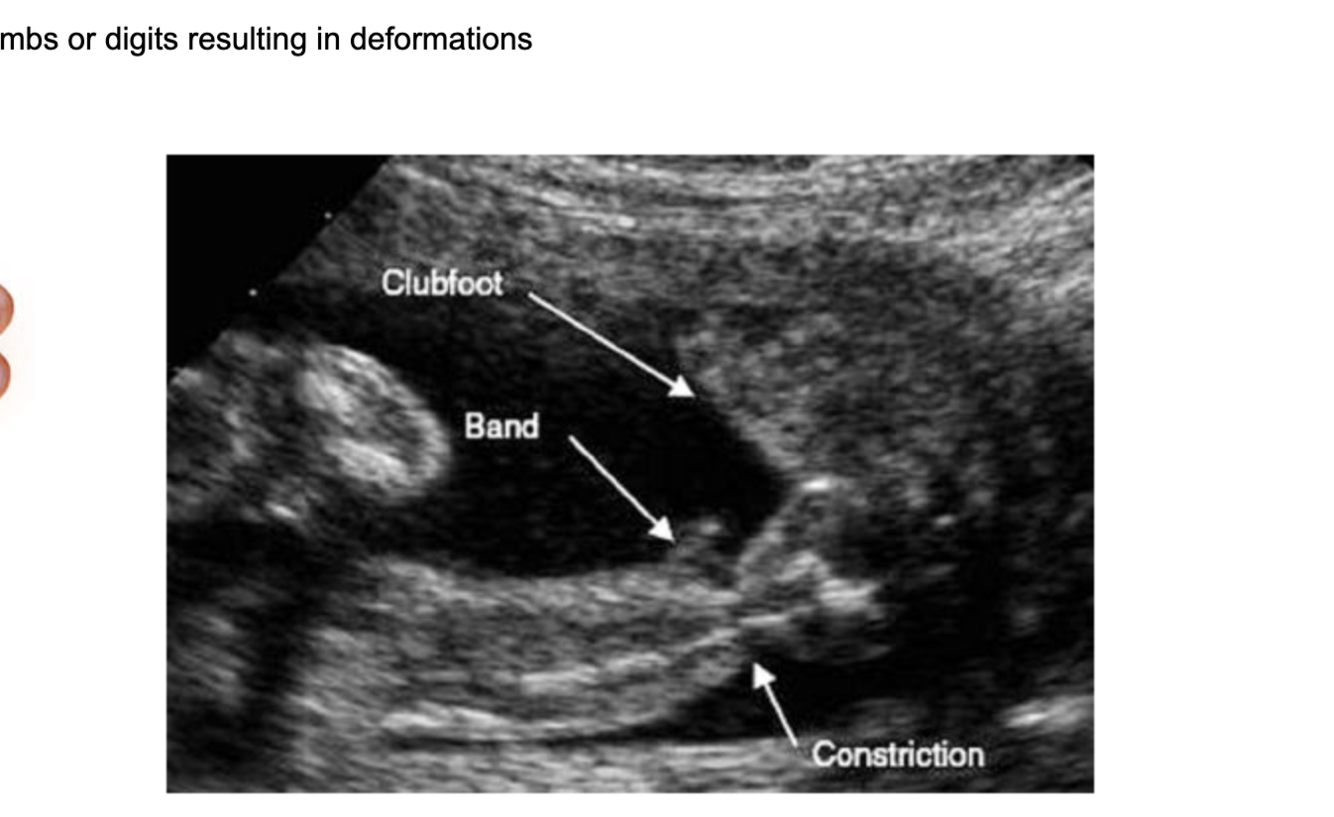

Tears in the amnion may result in amniotic bands that encircle the fetal limbs or digits resulting in deformations.